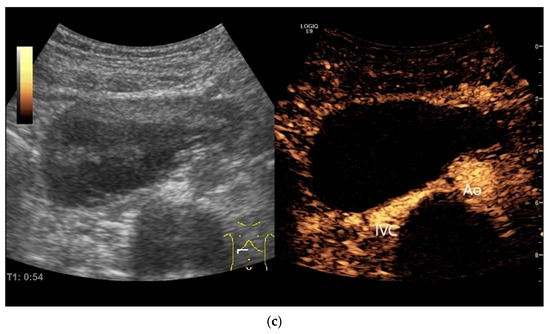

Figure 21.

Duodenal wall hematoma after gastroscopy with forceps biopsy under dual antiplatelet therapy. Clinically, there was pain and lumen obstruction. Evident focal hypoechoic wall thickening (between the markers) with lumen obstruction (a), for which there was no correlation in the previous gastroscopy. No evidence of macro vessels in CDI (b). In CEUS, the mass is smoothly defined and completely non-enhanced (c). IVC—inferior caval vein, Ao—aorta.